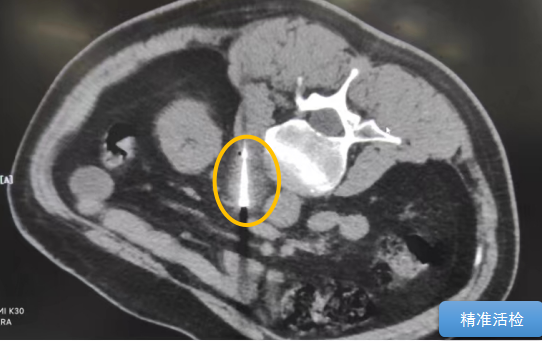

這個(gè)患者病變位置刁鉆,穿刺難度大,冷凍消融的難點(diǎn)在于既要不損傷膈肌和肺組織,同時(shí)又要盡最大可能完全消融腫瘤。術(shù)前陳寶瑩主任、李鐵柱教授、兀云飛醫(yī)生詳細(xì)設(shè)計(jì)進(jìn)針路徑、布針計(jì)劃,術(shù)中微創(chuàng)團(tuán)隊(duì)協(xié)調(diào)配合,李鐵柱教授仔細(xì)操作,精準(zhǔn)到位,順利完成兩個(gè)病變的布針,遂啟動(dòng)治療,先快速降溫到-150多度,再升溫至15?,經(jīng)過(guò)兩個(gè)循環(huán)反復(fù),即刻觀察到病變完全被冰球覆蓋,同時(shí)周?chē)K器無(wú)損傷,術(shù)中患者幾乎沒(méi)有疼痛,還和醫(yī)生聊起了天。

術(shù)中冰球形成